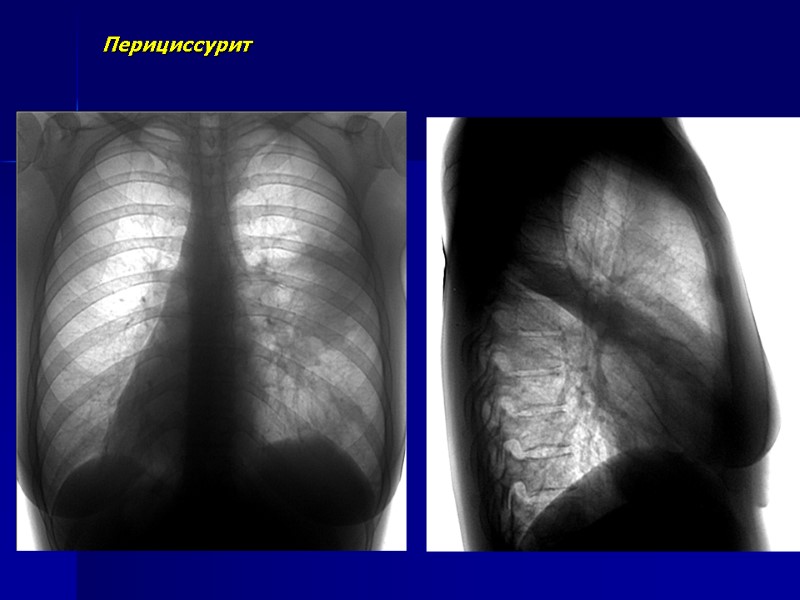

Перициссурит